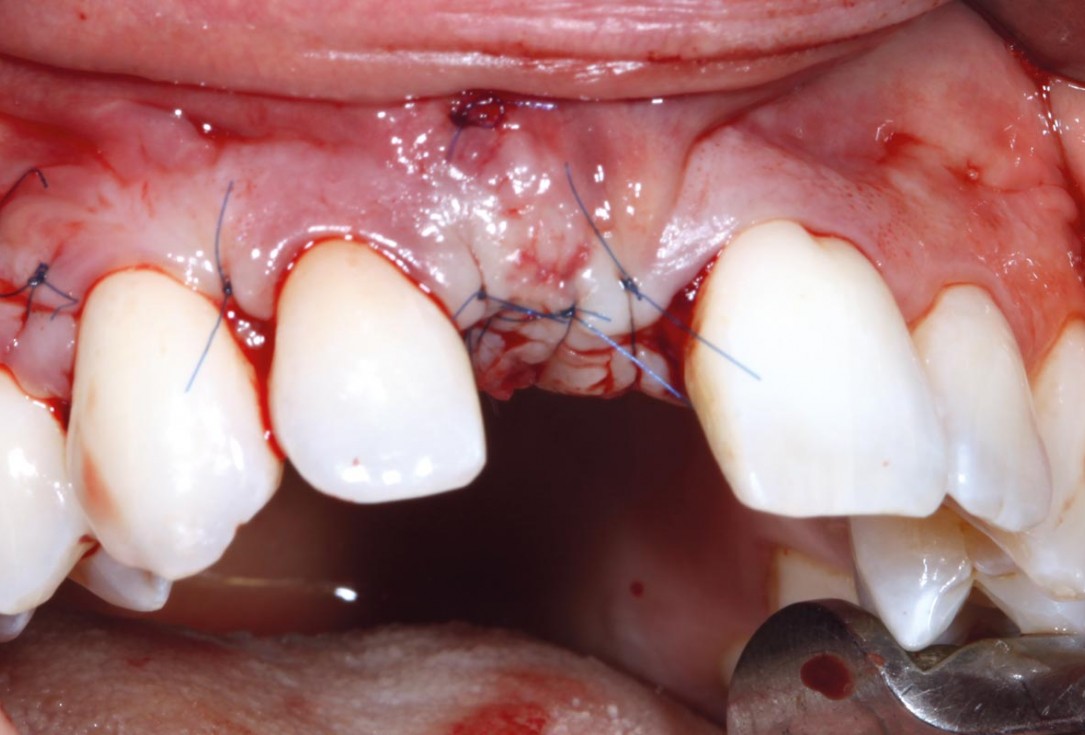

6/11 - Horizontal matress suture and tension-free wound closuremaxgraft® cortico at combined defect palatally and facially - Dr. K. Höckl

maxgraft® cortico at combined defect palatally and facially - Dr. K. Höckl

1/11 - Clinical situationmaxgraft® cortico at combined defect palatally and facially - Dr. K. Höckl